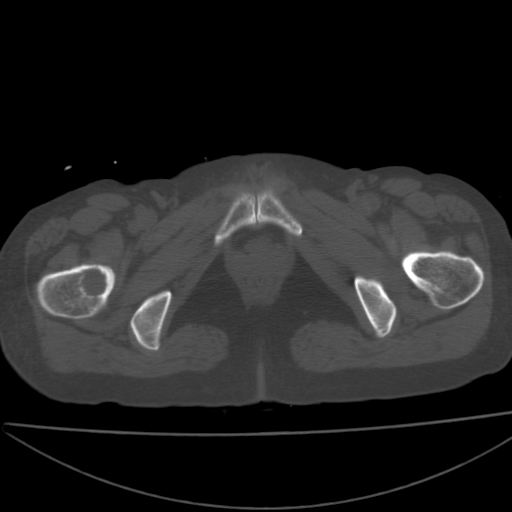

以下是引用xiaoniu在2008-9-6 8:22:00的发言:[br]右侧股骨颈囊性低密度,囊壁边缘硬化,中年妇女,首先考虑:骨囊肿。其次考虑动脉瘤样骨囊肿。[br][br][br][本贴已被 xiaoniu 于 2008-9-6 9:04:54 修改过]